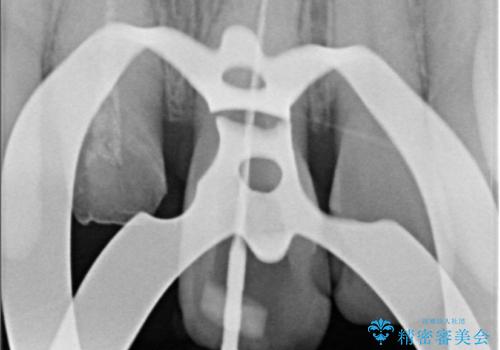

- 気を失って転倒し、前歯をぶつけたことをきっかけに「かかりつけ医で抜歯と診断された」との主訴で来院された患者様です。

レントゲン撮影や顕微鏡下での精査、メチレンブルーによる染色検査を行った結果、破折線は認められず、保存可能と判断しました。

精密根管治療を行い、その後オールセラミッククラウンで審美的に修復しています。あわせてホワイトニングとエアフローによるクリーニングも行い、自然で美しい仕上がりとなりました。